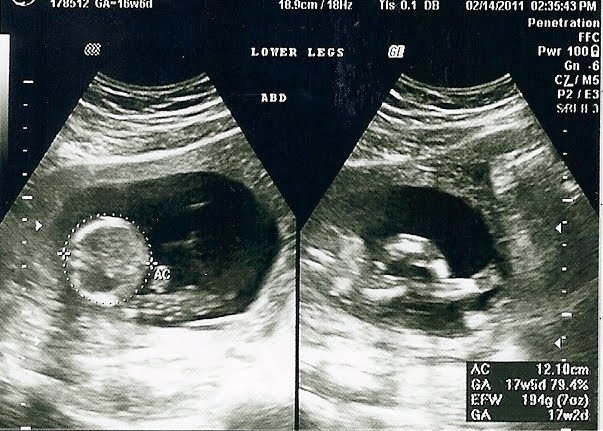

The top picture is his head and spine, the middle is his "credentials" (as Dallas called them), and the bottom right is his legs and feet. This ultrasound was done at 17 weeks to measure everything since my uterus was "too big" for my original due date. Turns out that I'm just small, which makes my inside girl parts (and inside boy, I guess) seem bigger by comparison. Dresden was about the size of my palm from his head to his rump. He weighed 7 ounces.